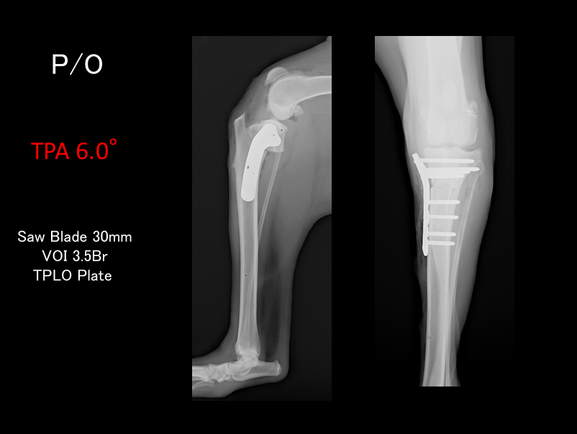

整形外科